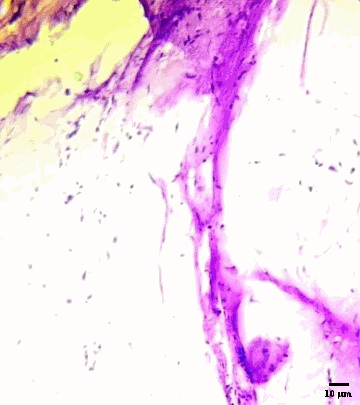

The histological section of hoof tissue infected with candida albicans are shown in fig. 8. The tissue displays abundant fungal structures, including pseudohyphae, blastospores (yeast cells), and hyphal elements, indicating active fungal invasion and tissue disruption [26]. In contrast, Fig. 9 (hoof tissue treated with the optimized nail serum) reveals a marked reduction in fungal structures, with no visible pseudohyphae, blastospores, or hyphae. The hoof tissue architecture appears preserved, indicating that treatment with the serum significantly decreased fungal growth. Similarly, fig. 10 (hoof tissue treated with the marketed formulation) also shows the absence of fungal elements, maintaining the integrity of the tissue. The substantial reduction in fungal colonization observed in fig. 9 demonstrates that the developed nail serum effectively inhibits candida albicans growth. The histopathological results indicate that the serum formulation exhibits antifungal efficacy comparable to the marketed product, thereby supporting its potential use in treating fungal infections of the nail or hoof tissue.

Fig. 10: Histopathology section of hoof nail tissue treated with the marketed formulation